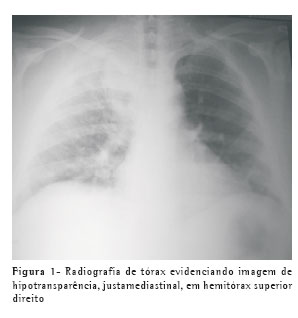

A radiografia de tórax, no momento da internação, evidenciou imagem de hipotransparência no terço superior do hemitórax direito (Figura 1). A tomografia computadorizada do tórax demonstrou imagem sugestiva de empiema pleural septado localizado em região paravertebral superior, no hemitórax direito (Figura 2). O paciente foi submetido à toracotomia exploradora póstero-lateral, em caráter de urgência, com drenagem das lojas empiemáticas e descorticação pulmonar. Permaneceu em ventilação mecânica por seis dias, recebendo alta da unidade de terapia intensiva no décimo dia de pós-operatório, com evolução satisfatória e regressão do quadro infeccioso. Após o desmame da ventilação mecânica e a extubação do paciente, quando ele estava consciente, foi observada a presença de ptose palpebral à direita. O paciente percebeu essa ptose no quinto dia após o início da instalação do quadro clínico e antes da internação hospitalar, fato confirmado por seus familiares (Figura 3). O paciente recebeu alta hospitalar no décimo quarto dia após a cirurgia, em bom estado geral. Durante o acompanhamento ambulatorial pós-operatório, o paciente apresentou, após dois meses, regressão total da ptose palpebral.